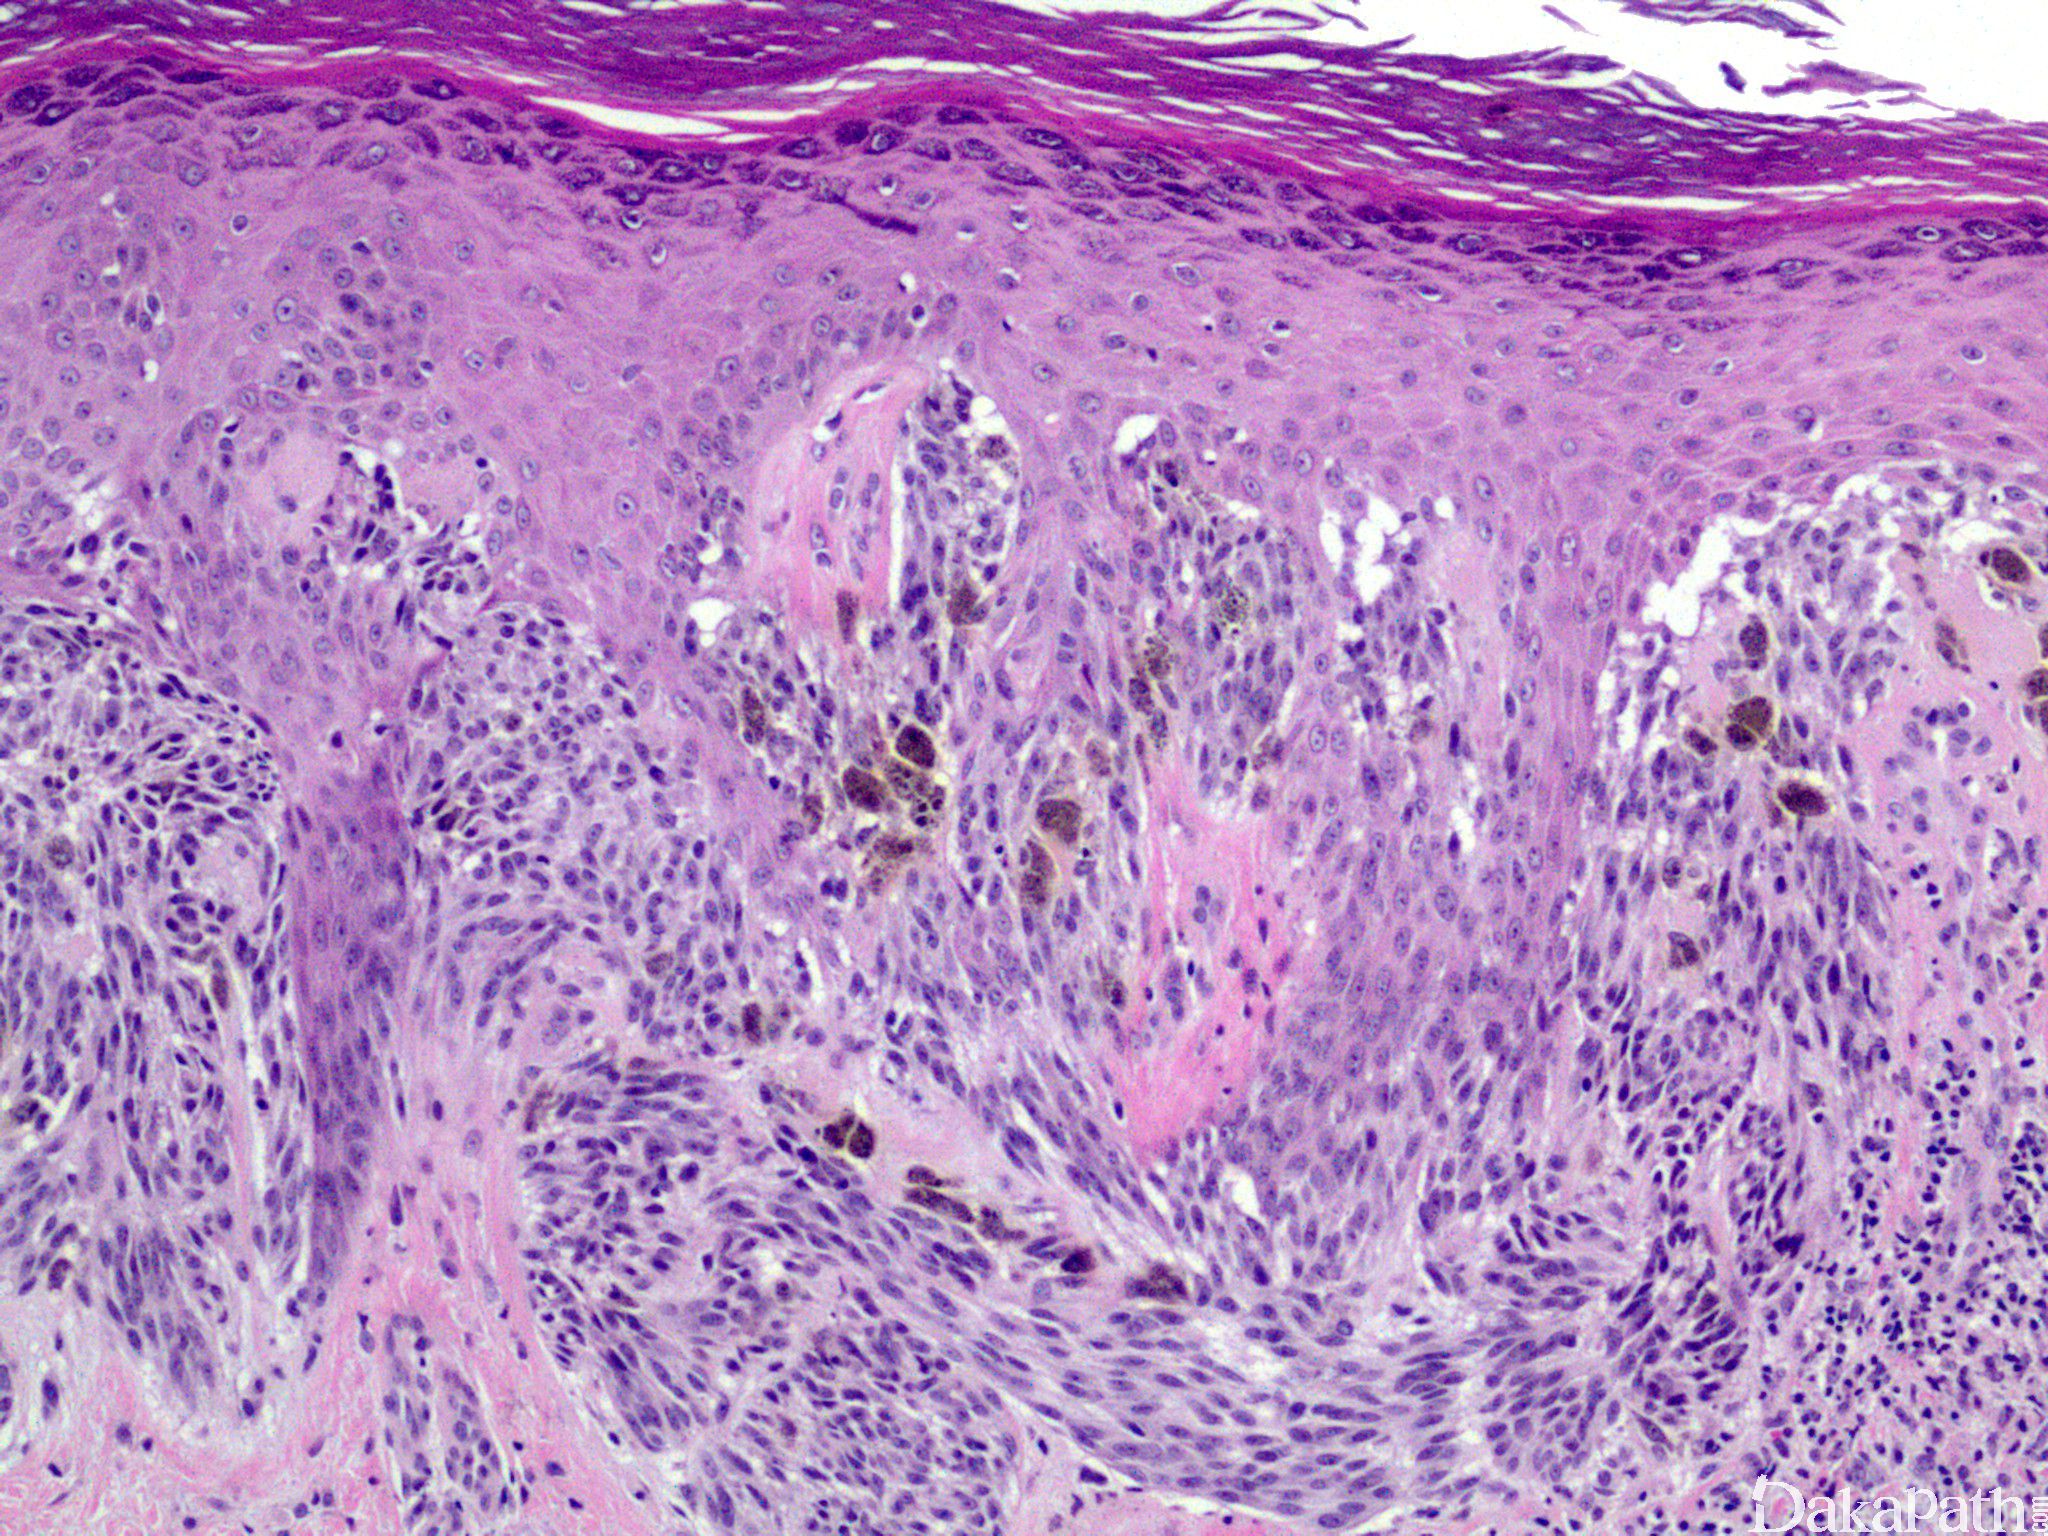

由大而肥胖的梭形和上皮样黑色素细胞组成;

细胞形态不定,从大的上皮样细胞到梭形细胞均可见到,有些病变以上皮样细胞为主,有些则以梭形细胞为主;

梭形细胞呈雪茄样,核大,核仁明显;

上皮样细胞单个散在分布,多角形,具丰富的嗜酸性胞质,核大,核仁明显,偶尔可见少量多核或显著核异型细胞,核分裂像多少不一;

表皮增生、表皮-真皮交界处可见粉红色均质小球(Kamino 小体);

交界性或复合性 Spitz 痣部分病例梭形细胞呈紧密束状排列,与上皮脚平行,如悬挂的香蕉一样;交界处黑色素细胞巢常见“裂隙”;可见核分裂,但通常很少见并且局限在细胞密集病变的表浅部位;